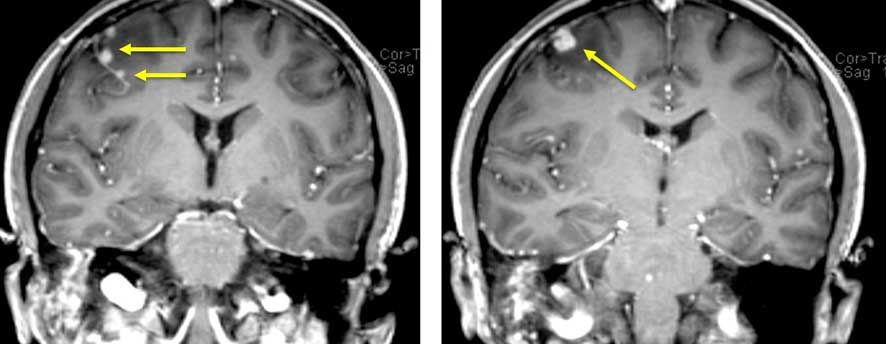

Central nervous system (CNS) tuberculosis (TB) is a rare but serious infectious disease caused by the bacteria Mycobacterium tuberculosis that can affect the brain, spinal cord, and meninges. It can manifest as meningitis, tuberculoma, abscesses, or encephalopathy, and can lead to severe complications if left untreated.